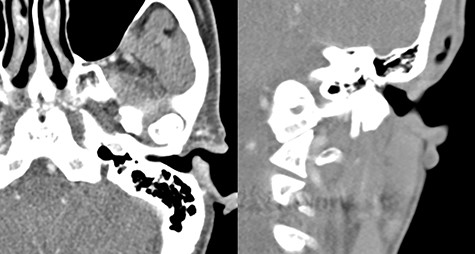

A 54-year-old woman visited our otorhinolaryngology clinic for a cystic mass in the left EAC with intermittent bleeding for several years. On physical examination, a 0.6 × 0.6 cm, soft, pinkish, cystic mass was observed in the posterior cartilaginous portion of the left EAC (Fig. 1). Facial computed tomography (CT) revealed an enhanced cystic mass in the posterior cartilaginous portion of the left EAC (Fig. 2). Considering a vascular tumor, surgical excision was planned because the patient had intermittent symptoms of bleeding.

A 0.6 × 0.6 cm, soft, pinkish, cystic mass in the posterior cartilaginous portion of the left external auditory canal.